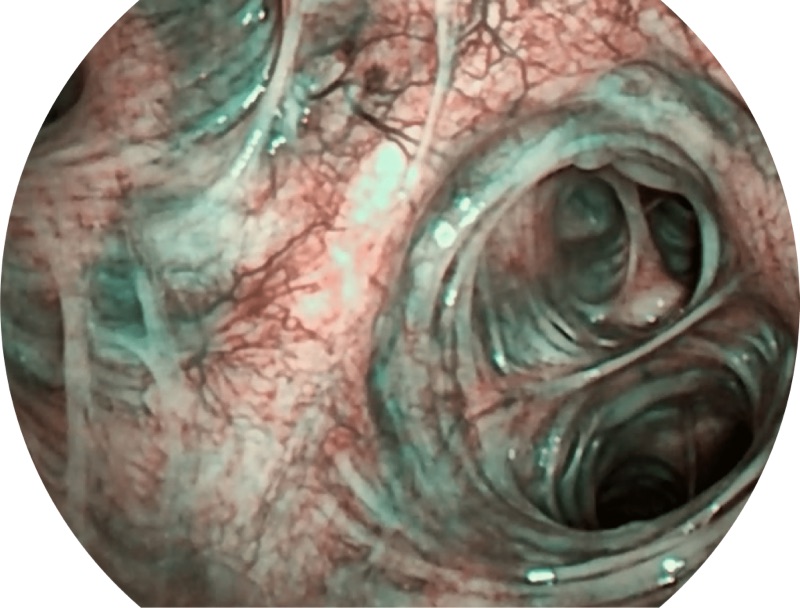

• 高清画质

帮助医生更加清晰地观察气管表面病灶

• SFI

• VIST